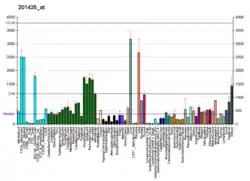

Aldehyde dehydrogenase, mitochondrial is an enzyme that in humans is encoded by the ALDH2 gene located on chromosome 12.[5][6] ALDH2 belongs to the aldehyde dehydrogenase family of enzymes. Aldehyde dehydrogenase is the second enzyme of the major oxidative pathway of alcohol metabolism. ALDH2 has a low Km for acetaldehyde, and is localized in mitochondrial matrix. The other liver isozyme, ALDH1, localizes to the cytosol.[7]

Most White people have both major isozymes, while approximately 50% of East Asians have the cytosolic isozyme but not a functional mitochondrial isozyme. A remarkably higher frequency of acute alcohol intoxication among East Asians than among Whites could be related to this absence of a catalytically active form of ALDH2. The increased exposure to acetaldehyde in individuals with the catalytically inactive form may also confer greater susceptibility to many types of cancer.[8]

The inactivating ALDH2*2 mutation is "the most common single point mutation in humans".[15] This mutation is found in very few White people, but about 50% of East Asians are heterozygous for this mutation. The ALDH2*2 allele encodes lysine instead of glutamic acid at amino acid 487,[16] distorting the NAD+ binding site.[17][18] ALDH2 assembles and functions as a tetramer and requires all four of its components to be active in order to metabolize acetaldehyde. People heterozygous for ALDH2*2 have only 10% to 45% enzyme activity, while those hymozygous for ALDH2*2 have as little as 1% to 5% remaining activity.[19]

Distribution

More recently, ALDH2 has been implicated in a number of pathways beyond alcohol metabolism. ALDH2 dysfunction is supposedly associated with a variety of human diseases including diabetes, neurodegenerative diseases, cardiovascular diseases and stroke, cancer, Fanconi anemia, pain, osteoporosis, and the process of aging.[15] The inactivating ALDH2 rs671 polymorphism, present in up to 8% of the global population and in up to 50% of the East Asian population, is associated with increased risk of cardiovascular conditions such as coronary artery disease, alcohol-induced cardiac dysfunction, pulmonary arterial hypertension, heart failure and drug-induced cardiotoxicity.[24]